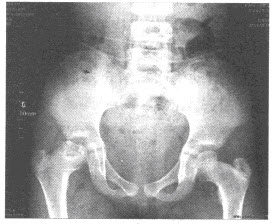

女,9岁,右髋部疼痛、跛行半年,无发热。结合骨盆平片,最可能的诊断为()

A:右髋关节结核

B:右髋关节化脓性关节炎

C:右股骨骨骺骨结核

D:右髋类风湿性关节炎

E:右股骨头骨骺缺血坏死